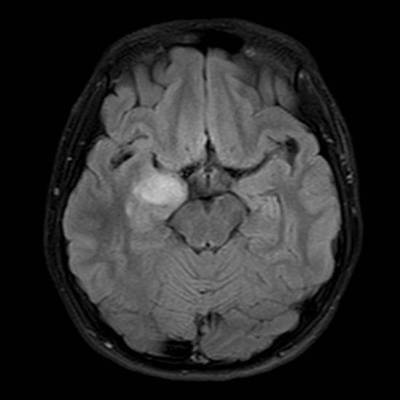

- A) Sağ temporal lob anteromedialinde silik sınırlı BT’de hipodens (ok), MRG’de T2AG ve FLAIR hiperintens (oklar), T1AG izo-hipointens (ok) sinyal özelliğinde ekspansil kitlesel lezyon izlenmektedir.

- B) Lezyon difüzyon görüntüde izo-hiperintens, ADC haritalamada hafif hiperintens izlenmiş olup (oklar) diffüzyon kısıtlılığı göstermemektedir. Lezyonun anterior kesiminde kontrastlı serilerde yamalı kontrast tutulumları (oklar) mevcuttur. MR spektroskopide lezyon düzeyinden elde olunan multivoksel görüntülerde kolin pikinde artış ve NAA da azalma (oklar) dikkati çekmektedir. Kolin/kreatinin oranı 1.76 olarak ölçülmüştür.